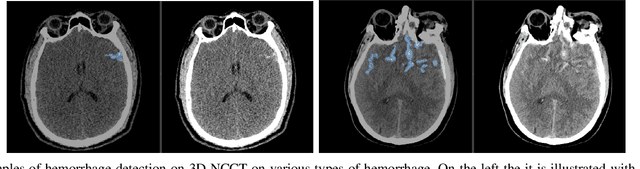

Abstract:Building accurate and robust artificial intelligence systems for medical image assessment requires not only the research and design of advanced deep learning models but also the creation of large and curated sets of annotated training examples. Constructing such datasets, however, is often very costly -- due to the complex nature of annotation tasks and the high level of expertise required for the interpretation of medical images (e.g., expert radiologists). To counter this limitation, we propose a method for self-supervised learning of rich image features based on contrastive learning and online feature clustering. For this purpose we leverage large training datasets of over 100,000,000 medical images of various modalities, including radiography, computed tomography (CT), magnetic resonance (MR) imaging and ultrasonography. We propose to use these features to guide model training in supervised and hybrid self-supervised/supervised regime on various downstream tasks. We highlight a number of advantages of this strategy on challenging image assessment problems in radiography, CT and MR: 1) Significant increase in accuracy compared to the state-of-the-art (e.g., AUC boost of 3-7% for detection of abnormalities from chest radiography scans and hemorrhage detection on brain CT); 2) Acceleration of model convergence during training by up to 85% compared to using no pretraining (e.g., 83% when training a model for detection of brain metastases in MR scans); 3) Increase in robustness to various image augmentations, such as intensity variations, rotations or scaling reflective of data variation seen in the field.